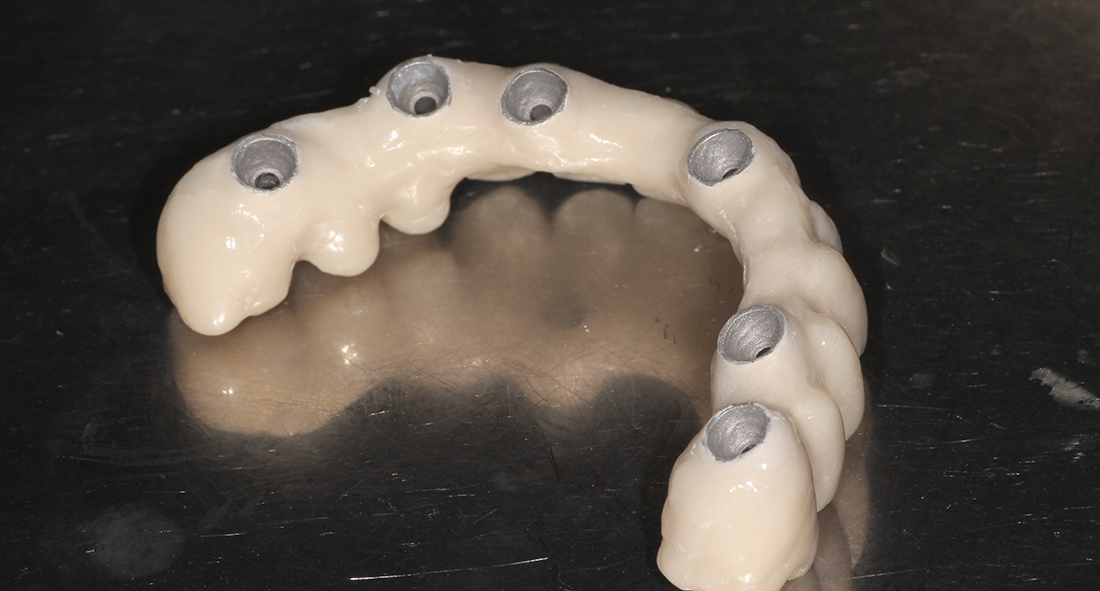

В таких ситуациях наиболее оптимальным решением является установка дентальных имплантов и фиксация ортопедической конструкции при помощи винтов. В системе «ICX Templant» это организуется следующим образом: устанавливается дентальный имплант, в него вкручивается небольшая головка «мультиюнит», а сама ортопедическая конструкция фиксируется к головке винтом. Т.о. сразу после установки имплантов мы имеем возможность зафиксировать окончательные головки, изготовить временную конструкцию с винтовой фиксацией, и после периода интеграции имплантов, заменить ее на финальную ортопедию. Именно таким путем мы и пошли в данной клинической ситуации.

В данной ситуации мы зафиксировали шаблон, установили 6 имплантов системы «ICX Templant» (Германия), провели наращивание костной ткани, установили окончательные головки «мультиюнит» и сняли слепки для изготовления временной конструкции. Через несколько дней был готов металлопластмассовый протез с винтовой фиксацией на шести имплантах.